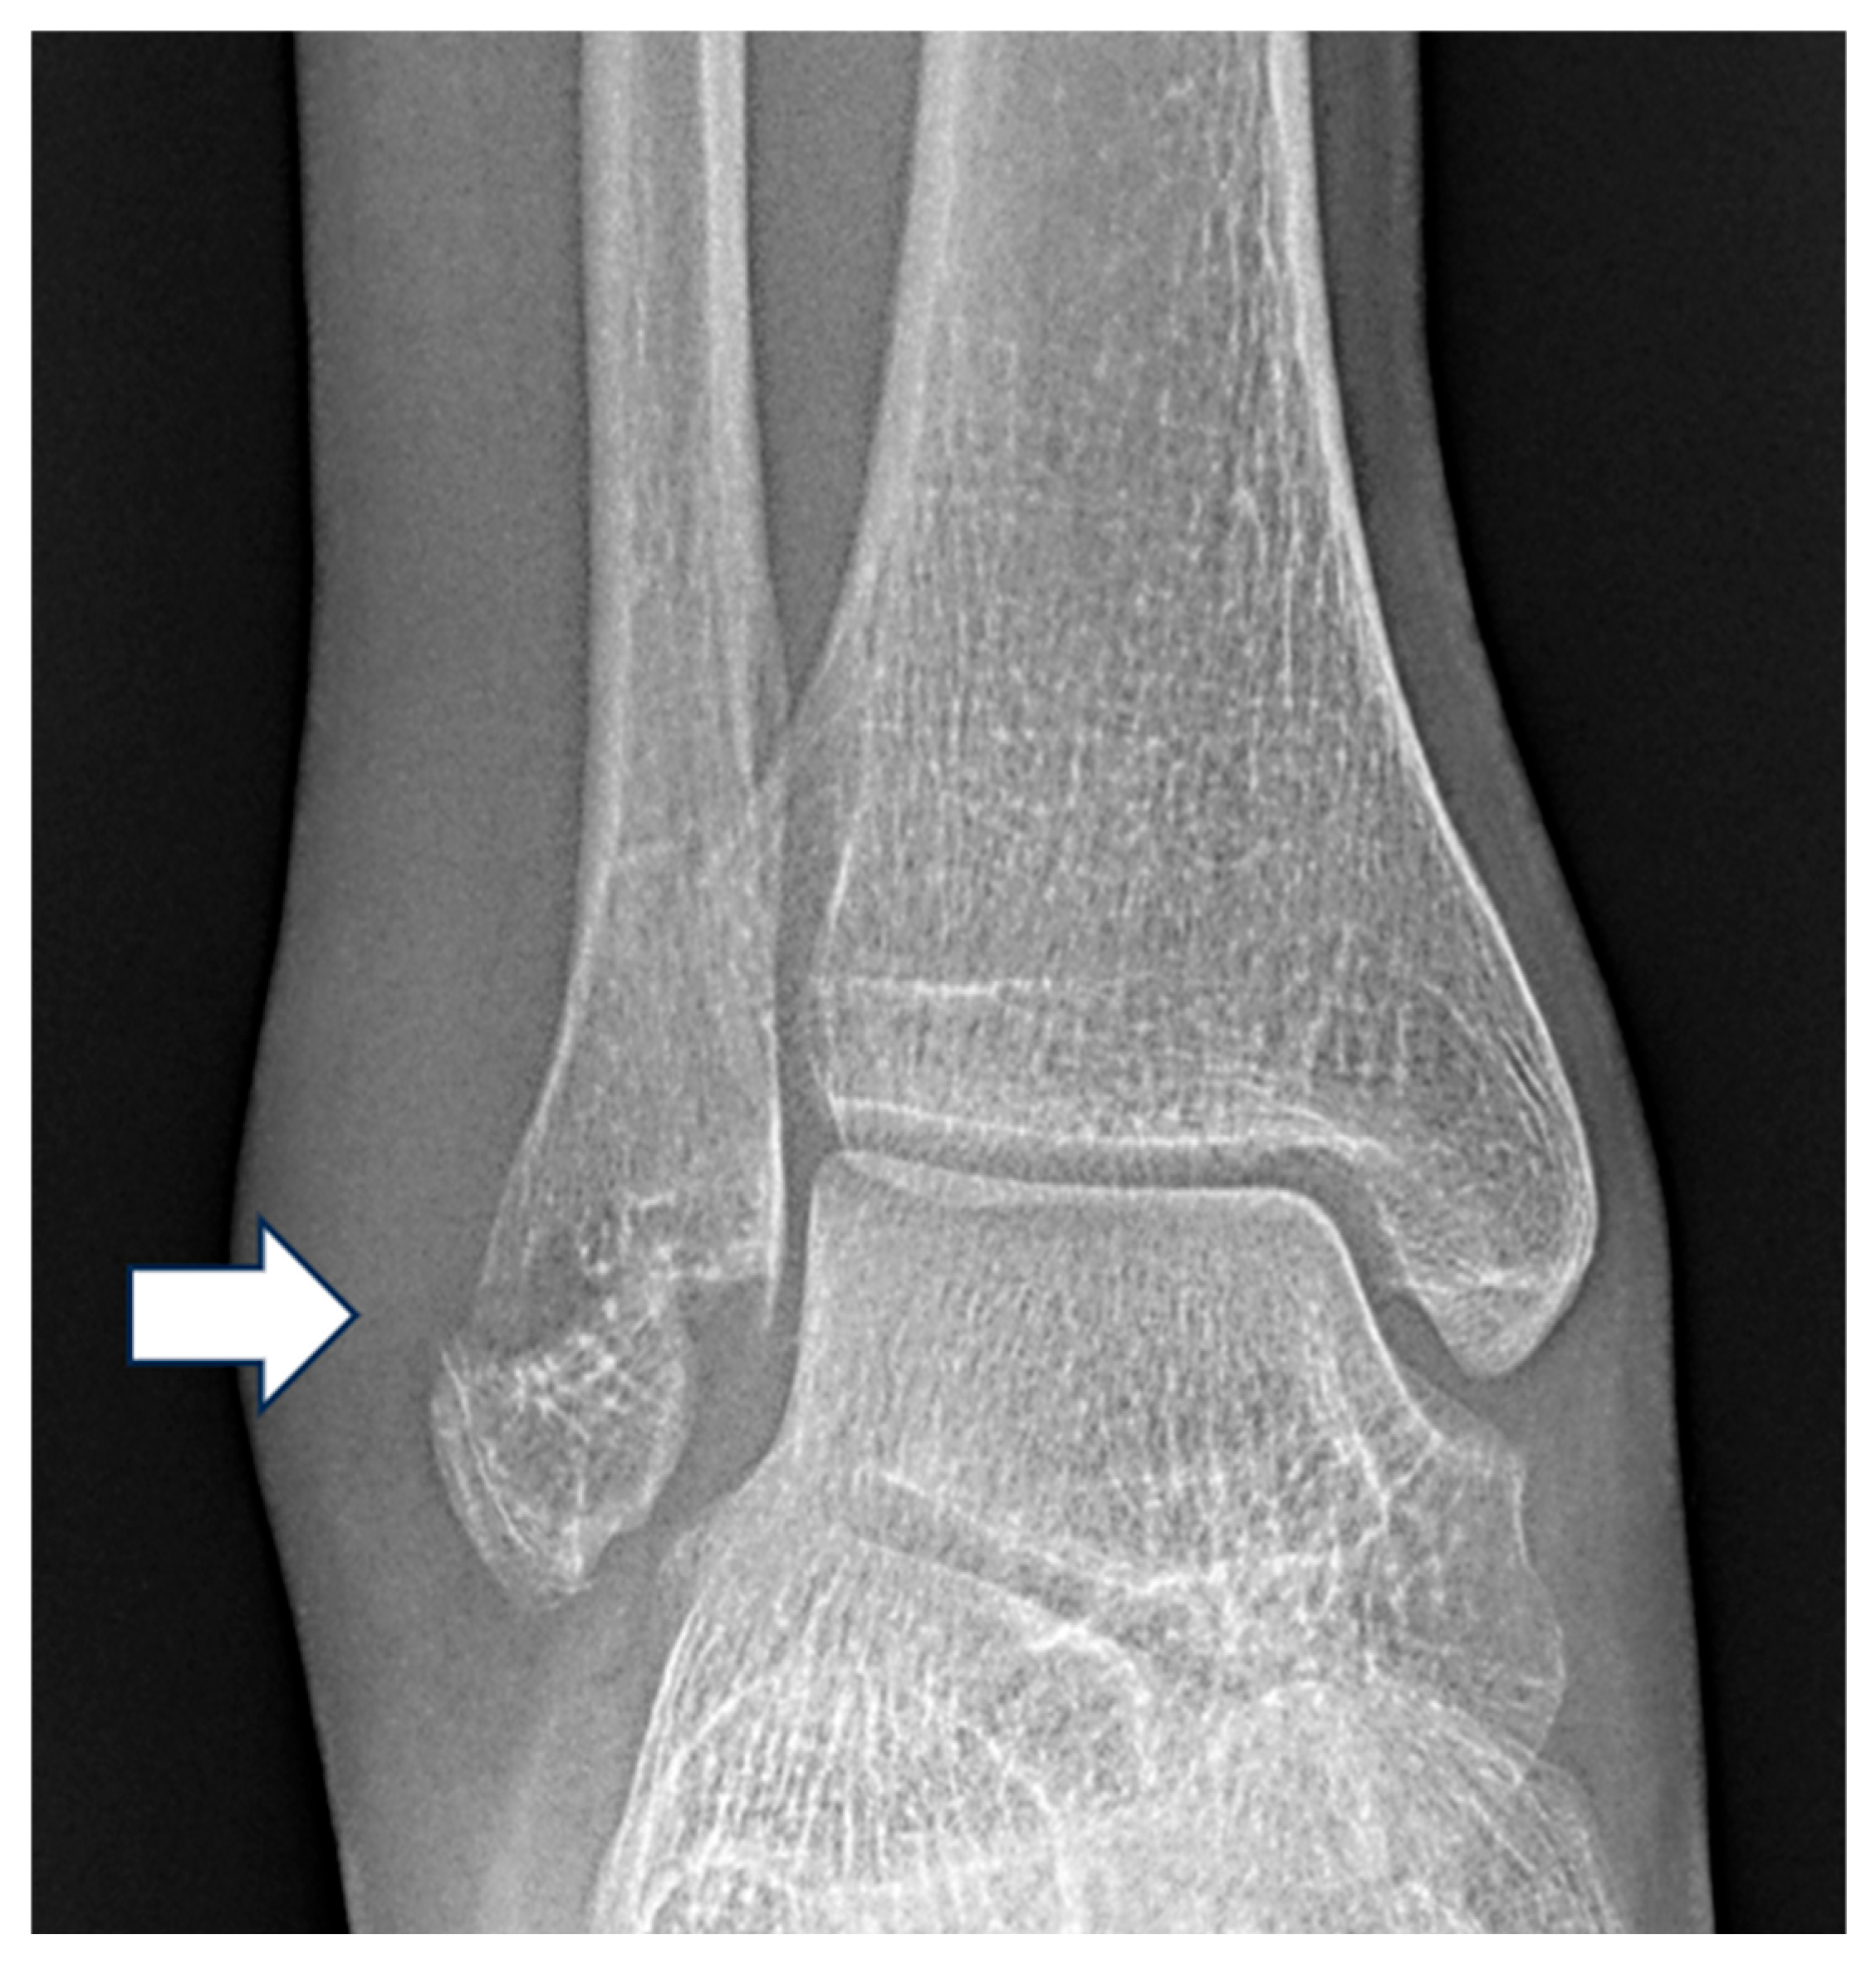

Correlation Between Weber Classification of Ankle Fractures and Medial Clear Space Widening on Radiography